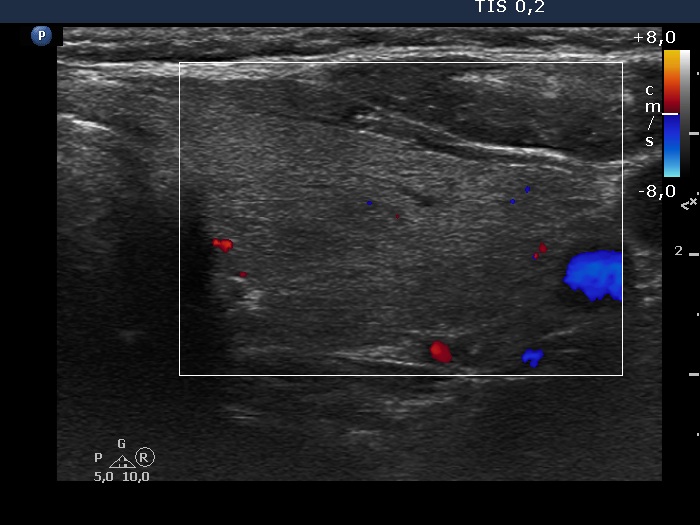

Left lobe, transverse view, color Doppler mode. The vascularity is scanty.